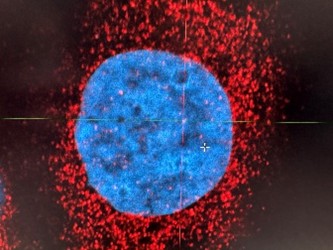

L’un de nos objectifs majeurs est d’identifier de nouvelles cibles thérapeutiques et de développer des approches innovantes pour éliminer plus efficacement les cellules tumorales.

La restauration de la mort cellulaire programmée

Certaines cellules cancéreuses échappent à l’apoptose (mort cellulaire). Nos travaux visent à rétablir ce mécanisme en ciblant des protéines clés, notamment MCL-1, grâce à des technologies innovantes comme les PROTAC, qui induisent la dégradation ciblée de protéines.

Identification de biomarqueurs

Nous recherchons des signatures moléculaires (transcriptomiques et protéiques) au sein des tumeurs permettant de prédire la réponse aux traitements. Un axe important concerne également les biomarqueurs circulants, comme les microARNs (miARNs) détectables dans le sang et capables de prédire la réponse aux traitements ou de suivre l’évolution de la maladie. Ces recherches s’inscrivent dans des essais cliniques multicentriques, à l’échelle nationale et internationale.